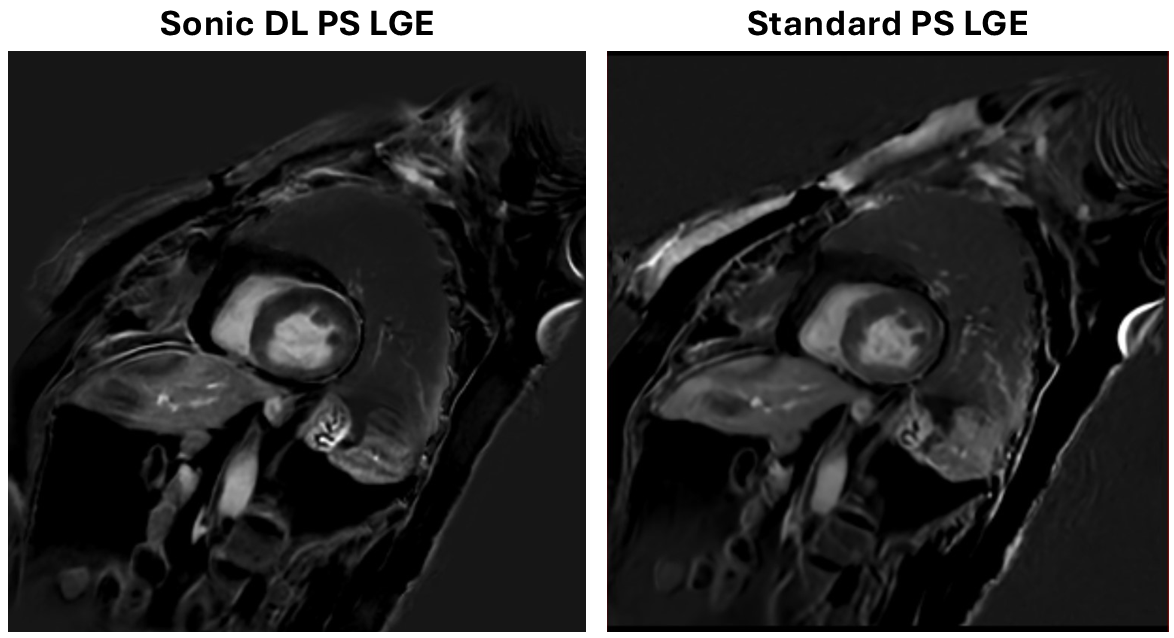

Results: There was no statistically significant difference between the two acquisitions in terms of image quality, with average Likert scores of ~4.1-4.2 from each reader for each acquisition. Artifact presence was also similar between the two acquisitions. The highly accelerated version was relatively more preferred by both readers (Reader 1: 18 vs. 12 with 27 no preference; Reader 2: 23 vs. 11 with 23 no preference). Figures 1 and 2 shows example images for patients with and without any visible abnormalities, respectively.

Figure 2: Comparison of Sonic DL and standard PS LGE acquisitions in a patient without an abnormality. A representative slice is shown for each acquisition from the same patient.

Figure 2: Comparison of Sonic DL and standard PS LGE acquisitions in a patient without an abnormality. A representative slice is shown for each acquisition from the same patient.

Figure 2: Comparison of Sonic DL and standard PS LGE acquisitions in a patient without an abnormality. A representative slice is shown for each acquisition from the same patient.

Figure 2: Comparison of Sonic DL and standard PS LGE acquisitions in a patient without an abnormality. A representative slice is shown for each acquisition from the same patient.